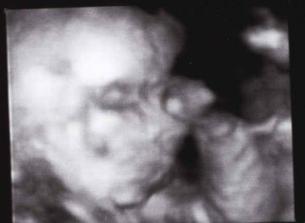

16.9.2008 jsme byli na 3D UTZ byla to nádhera...máme DVD a několik foteček Kubíčka...má už 710 g a měří 30 cm..pořad je to stydlín a nechtěl se nám pořádně ukázat, ale něco málo se paní doktorce podařilo nafotit...hlavně že je všechno v pořádku a Kubík se má čile k světu......